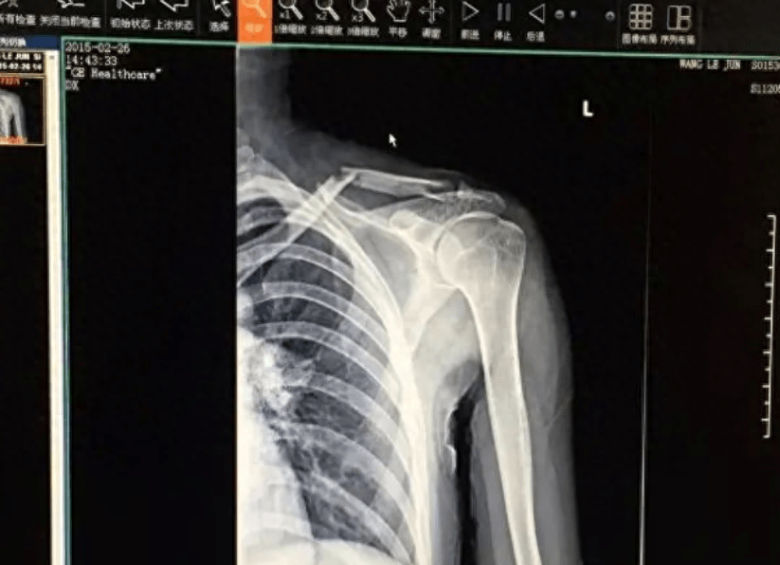

사진 보면, 그래요.. 정말 사고로 인해서 쇄골 골절, 흉터..

심각해요..ㅜㅜ

워낙 심하게 쇄골이 부러져서 통증도 엄청 심했고,

부상이 심해서 수술을 받아야 했고, 쇠못 7개를 꽂았는데,

왼쪽 귀가 거의 들을 수 없게 되었다고 해요.

쇄골이 부러졌다는 글과 부상, 치료 사진을 올리며,